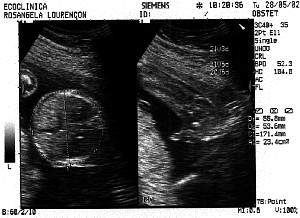

3rd Session - 28th May 2002

Week: 21

Size: Around

25 cm

Obs: IT'S A BOY !

Look this head. A genius :)

Laid back, hangin in there.